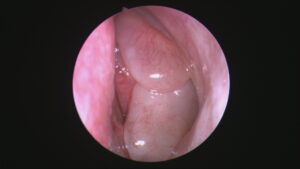

Buruna yönelik endoskopik cerrahi öncelikle kronik sinüzitin tedavisi için tanımlanmıştır. Ancak zamanla radyolojik ve dijital görüntülemenin gelişmesi ve tecrübenin artması ile sinüslerin ve kafa tabanının tümör cerrahisi, ensefaloseleksizyonu, beyin omurilik sıvı kaçaklarının burundan tamiri, gözyaşı kanalı tıkanıklığı tedavisi, bazı göz hastalıklarının burundan endoskopik yolla cerrahi tedavisi, koanalatrezi açılması gibi geniş bir endikasyon alanına yayılmıştır. Endoskopik kafa tabanı ekiplerinin uyguladığı kollektif yöntemle kafa tabanında yerleşmiş birçok tümörün tedavisi kraniotomi yapılmadan burundan yapılabilmektedir. Bu yöntem ile yapılan ameliyatlarda görüntü daha kaliteli ve büyük olduğu için tümörün tamamı hastaya en az hasar ile çıkarılabilmekte ve hastanede kalma ve iyileşme süresi de önemli ölçüde azalmaktadır.